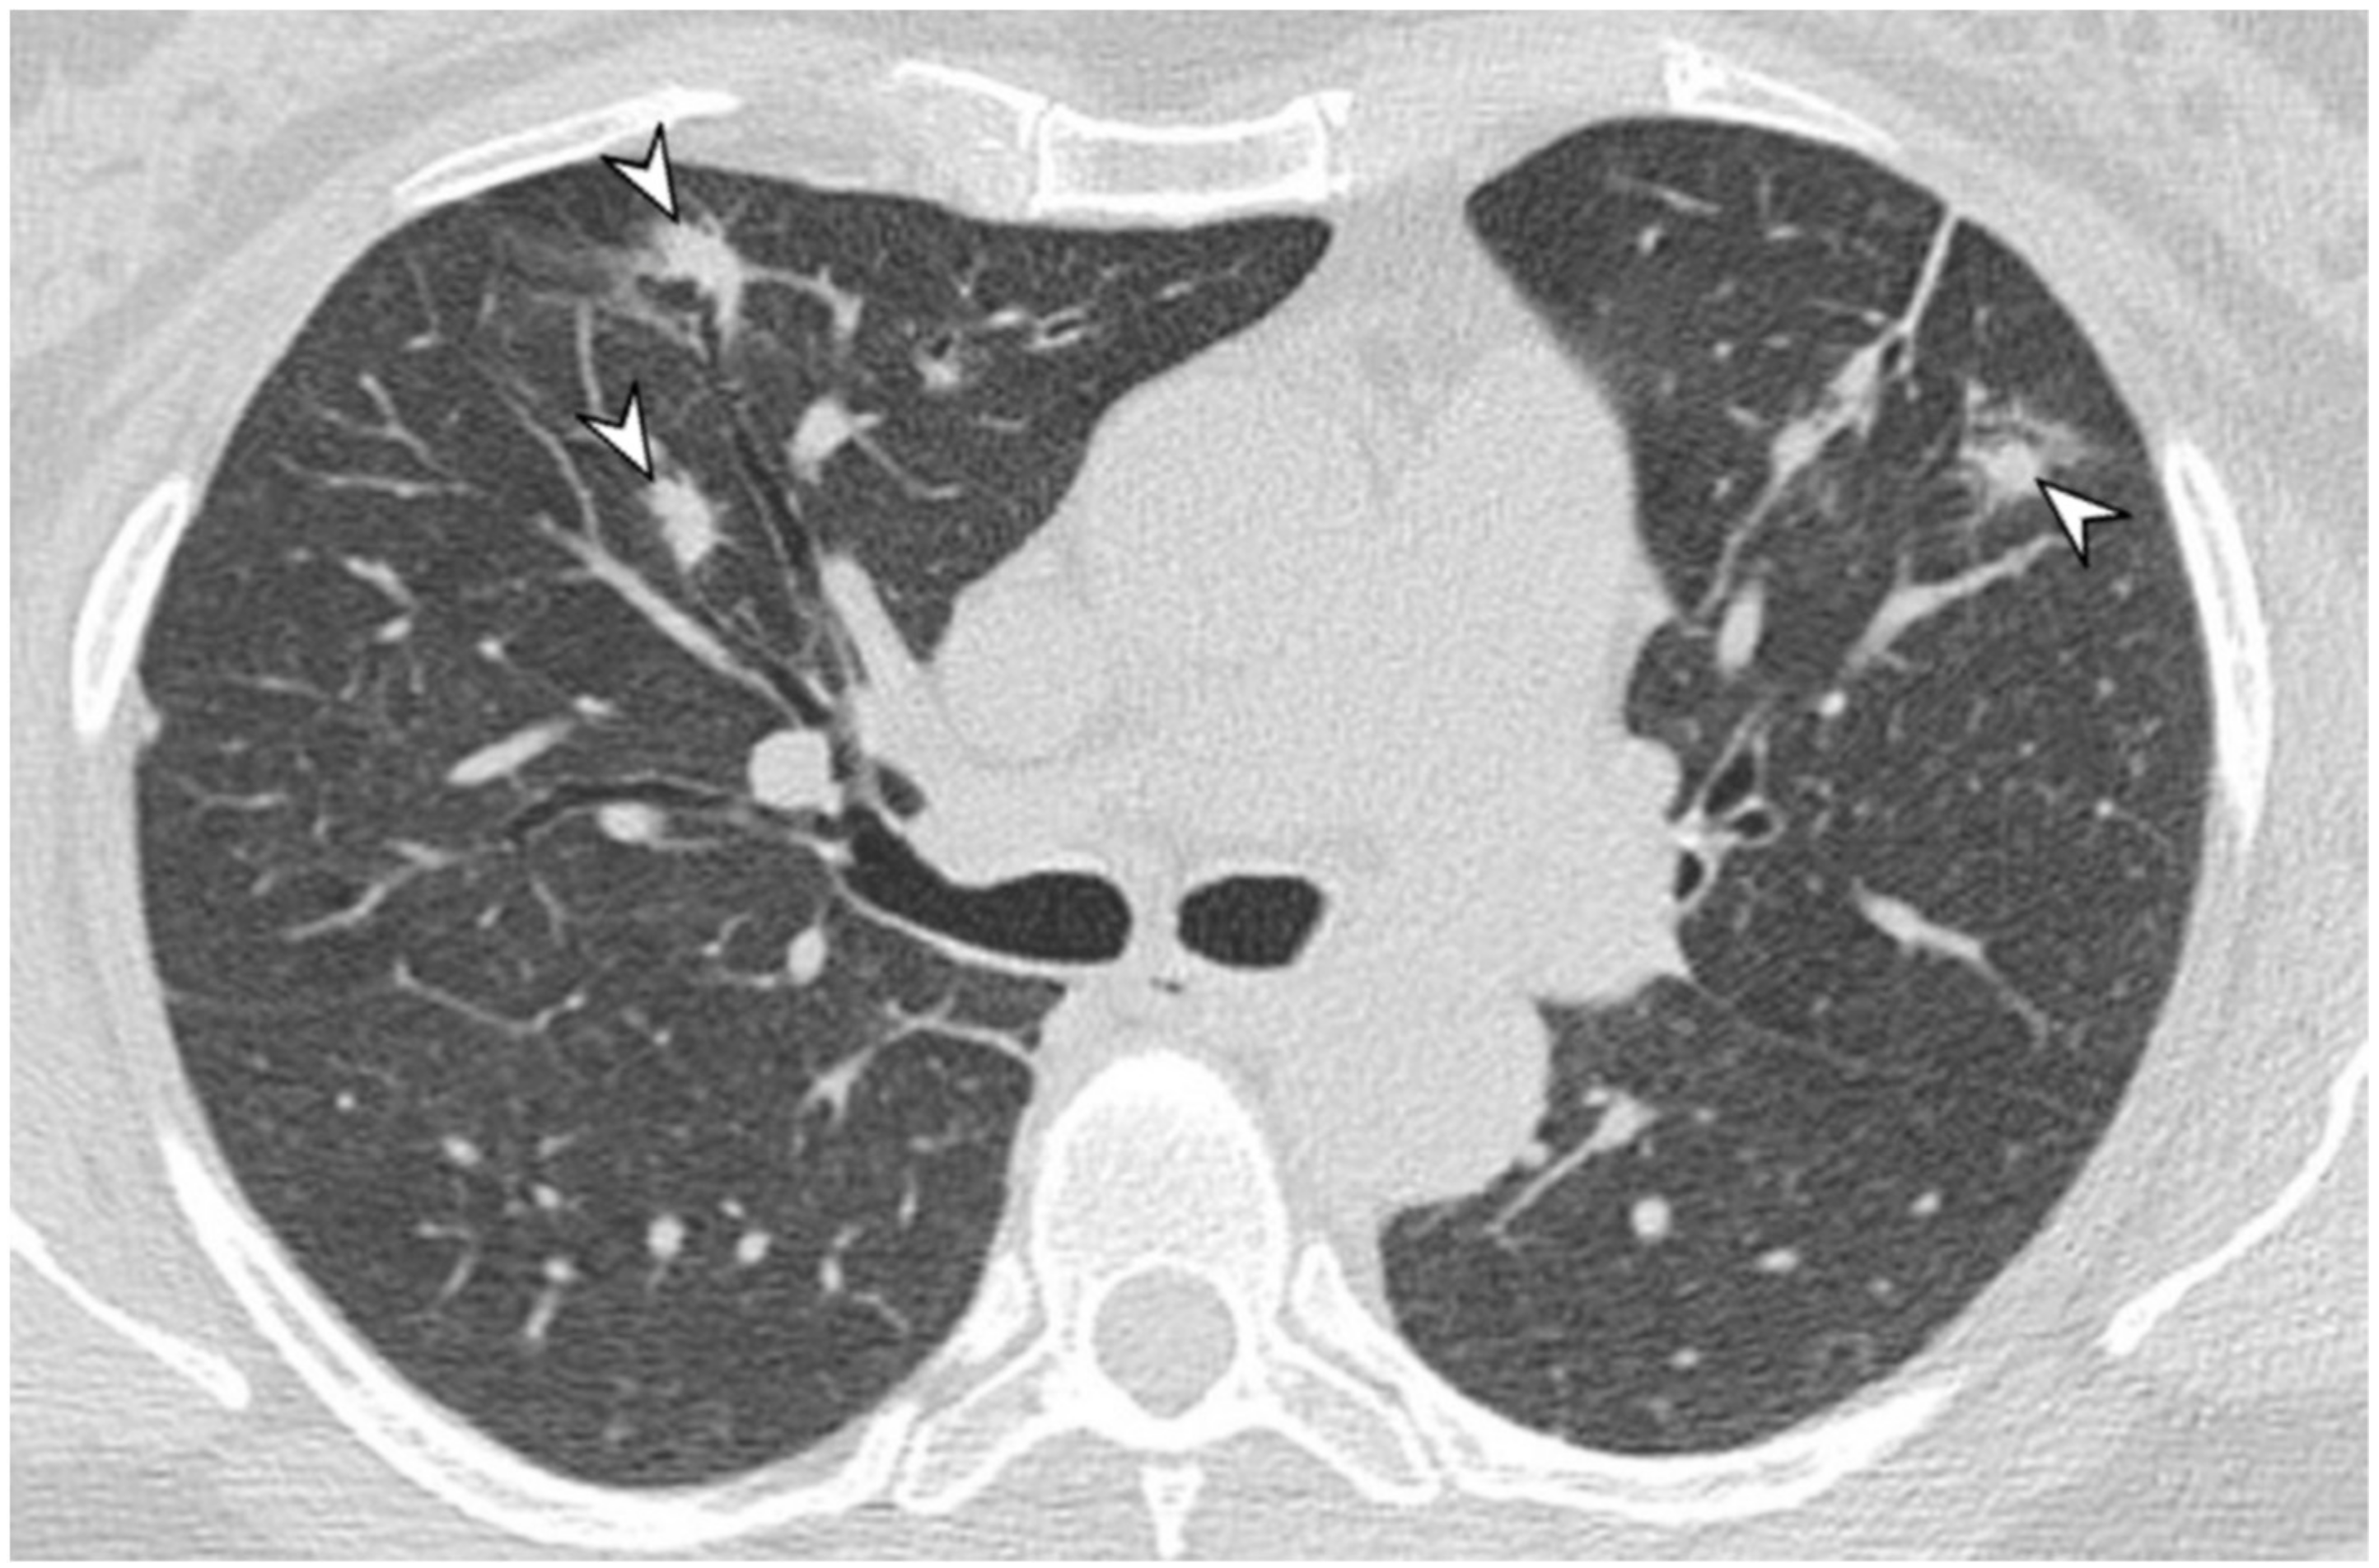

2.3. Microscopic Polyangiitis (MPA)

| MPA | GGOs due to hemorrhagic alveolitis (common); consolidation, nodules with centrilobular distribution (less common) |

| GPA | Solid nodules, GGOs due to hemorrhagic alveolitis (common); halo sign, crazy paving (less common) |